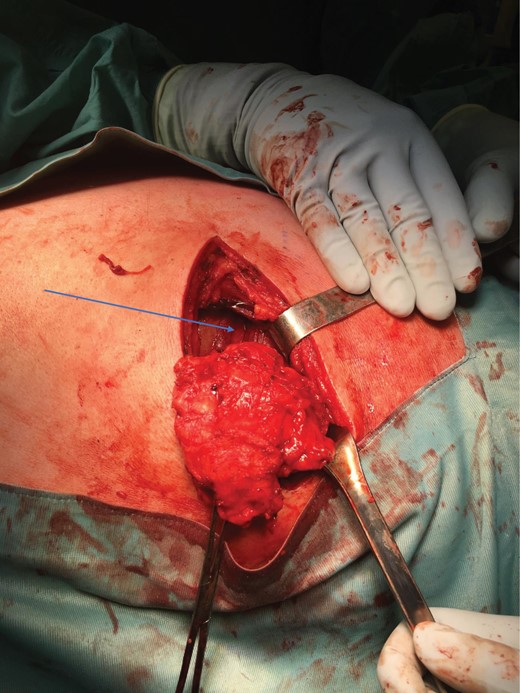

Surgery was uneventful but the tumour was quite deep below the lattisimus dorsi and serratus anterior muscles, and lying on the posterior rib cage (Figs 5–7).

Tumour exposure(forceps) below the lattisimus dorsi (blue arrow).

Post-operatively he developed a wound haematoma that was managed conservatively and eventually resolved (Figs 8 and 9).